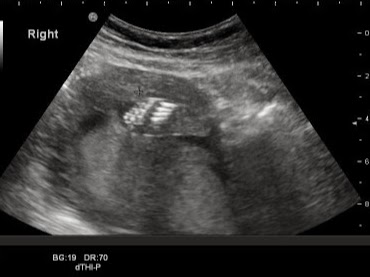

最後放上幾張QQ的高層次照片給各位叔叔阿姨伯伯們看一下

不過我只能說,真的都是「部位」,不是甚麼寫真XD

右手掌(五支手指頭還有分明的指節)

ET照!!是眼睛跟鼻子啦,大家一定看不出來,所以我註解了XD

仰著拍,就算是美女也不美 大家不要取笑她 噗哧

右腳掌(數一下也有五根)

這算是難得的照片了XD 主要是看他整個胸腹部

baby的肚子都好大

完整的脊椎

是側面喔!!

還可以看到兩支手不知道在幹嘛

左耳。這好可愛XD